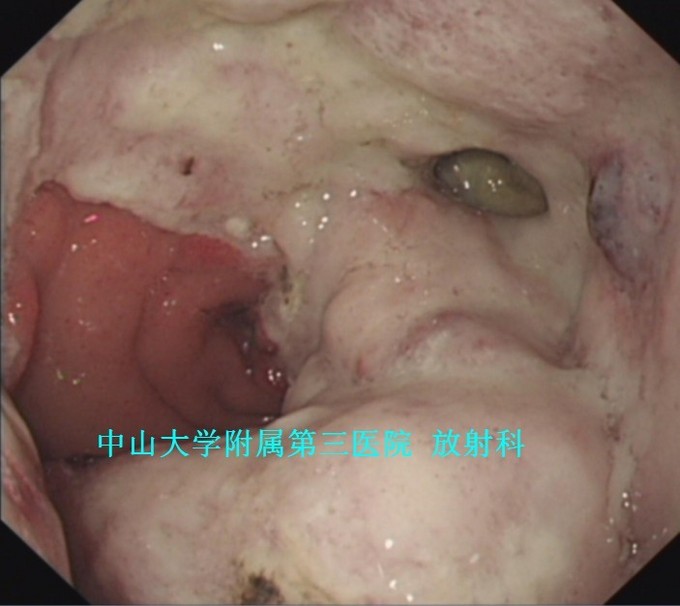

主诉:反复上腹痛1月,黑便1周 病史:46岁女性,急性起病。患者1月前反复出现进食后上腹部疼痛,伴恶心、呕吐。1周前出现黑便,伴头晕、乏力,抑酸、护胃、止血等处理后,症状缓解,门诊拟“上消化道出血”收入我科。

查体:腹软,上腹部轻压痛、无反跳痛,未触及包块。 辅查:1、胃镜:胃十二指肠恶性病变(待病理);2、上腹部CT:胃窦至十二指肠胃壁弥漫性增厚,考虑淋巴瘤可能性大。

诊断:胃淋巴瘤 治疗:入院排除手术禁忌证后,于全麻下行“剖腹探查术”,术中发现胃肿物无法切除并幽门梗阻,遂决定行“胃肿物活检术+胃空肠吻合术”,术后病理提示“B细胞源性非霍奇金性淋巴瘤”,免疫组化示“CK(-),CEA(-),Vim(部分+),CD3(部分+),CD45RO(部分+),CD20(+),CD79α(+),CD56(-),TIA1(散在+),CK20(-),Ki-67(40%+),P53(+)。”。建议转血液科进行下一步内科治疗,患者拒绝转科并签字出院。